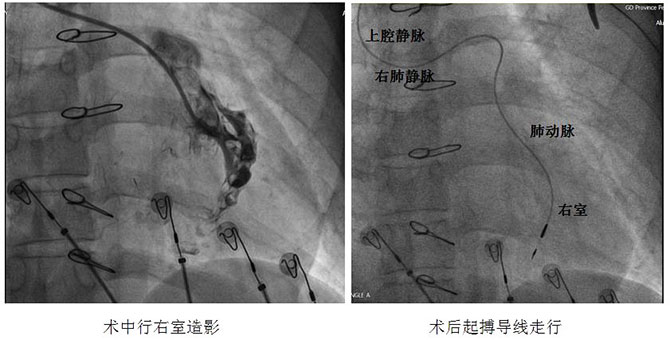

手术当日,主刀医师方咸宏主任经过数次更换导丝,配合特殊鞘支撑,历时2个多小时,顺利将普通细电极从左锁骨下静脉、上腔静脉、右肺动脉、肺动脉,经过两个直角弯后送至右室,最终成功为患者植入单腔起搏器,避免了患者的第三次开胸,同时也开创了TECPC术后植入心内膜起搏器的先例。